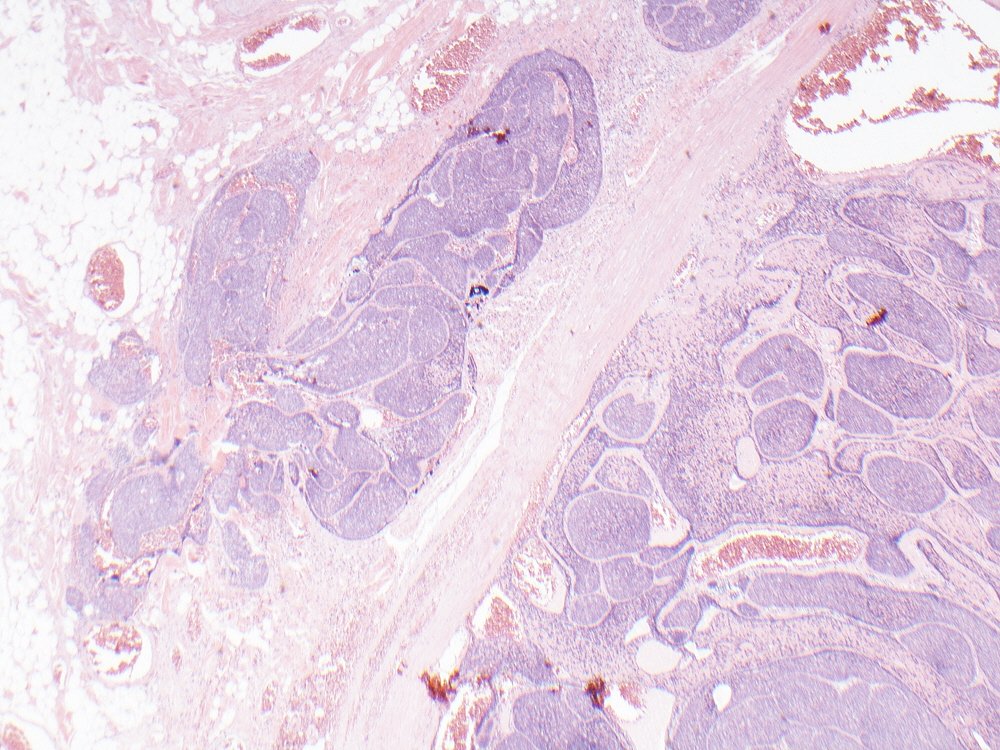

Basal cell adenocarcinoma of parotid showing jigsaw puzzle pattern, hyaline globules, focal squamous eddies and, most importantly, invasion into periglandular fat. Wide sampling essential to find those invasive foci #pathology #oralpath #entpath